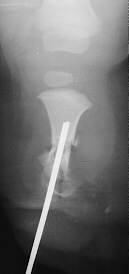

TREATMENT: The patient initially underwent a corrective tibial osteotomy and Boyd amputation of right foot. The postoperative course was complicated by the development of a nonunion at the osteotomy site necessitating resection of the pseudarthrosis with placement of K-wires. Following this, she did well ambulating with the use of a below-knee prosthesis.

FOLLOW-UP: At 9 years of age the patient was noted to have an increased flexion contracture about the knee with radiographs demonstrating a recurrent valgus deformity. She subsequently underwent a repeat tibial derotational osteotomy with correction of the valgus deformity. Her postoperative course was uncomplicated. Currently she is 17 years old and ambulates well with the use of a custom below-knee PTB prosthesis with a carbon copy foot.